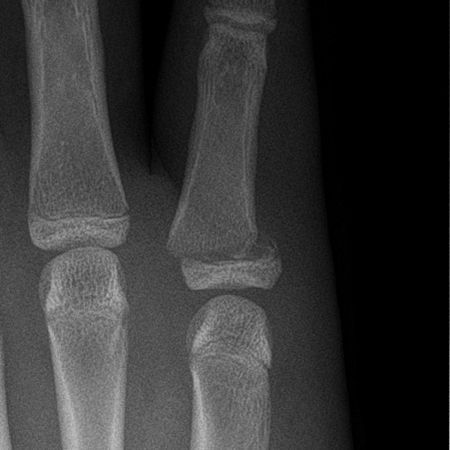

@RadMasterclass

TRAUMA X-RAY 72: Injury to hand in a child. What is the eponymous fracture? Answer https://t.co/cedJdlFoPp